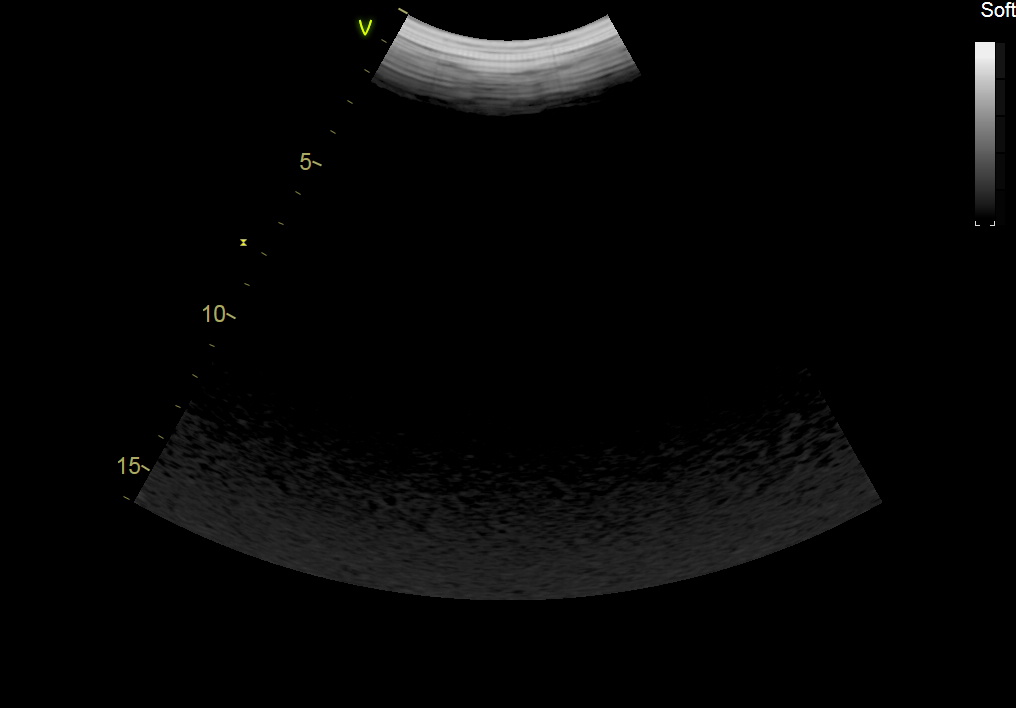

GE C1-6-D Abdominal Convex Refurbished

GE Convex C1-6-D Abdominal

Intended use

Abdominal and Women’s Health

Frequency Range

6 – 1 MHz

GE C1-6-D Abdominal Convex

Frequency Range: 6 – 1 MHz

GE C1-6-D Abdominal Convex for Abdominal and Women’s Health